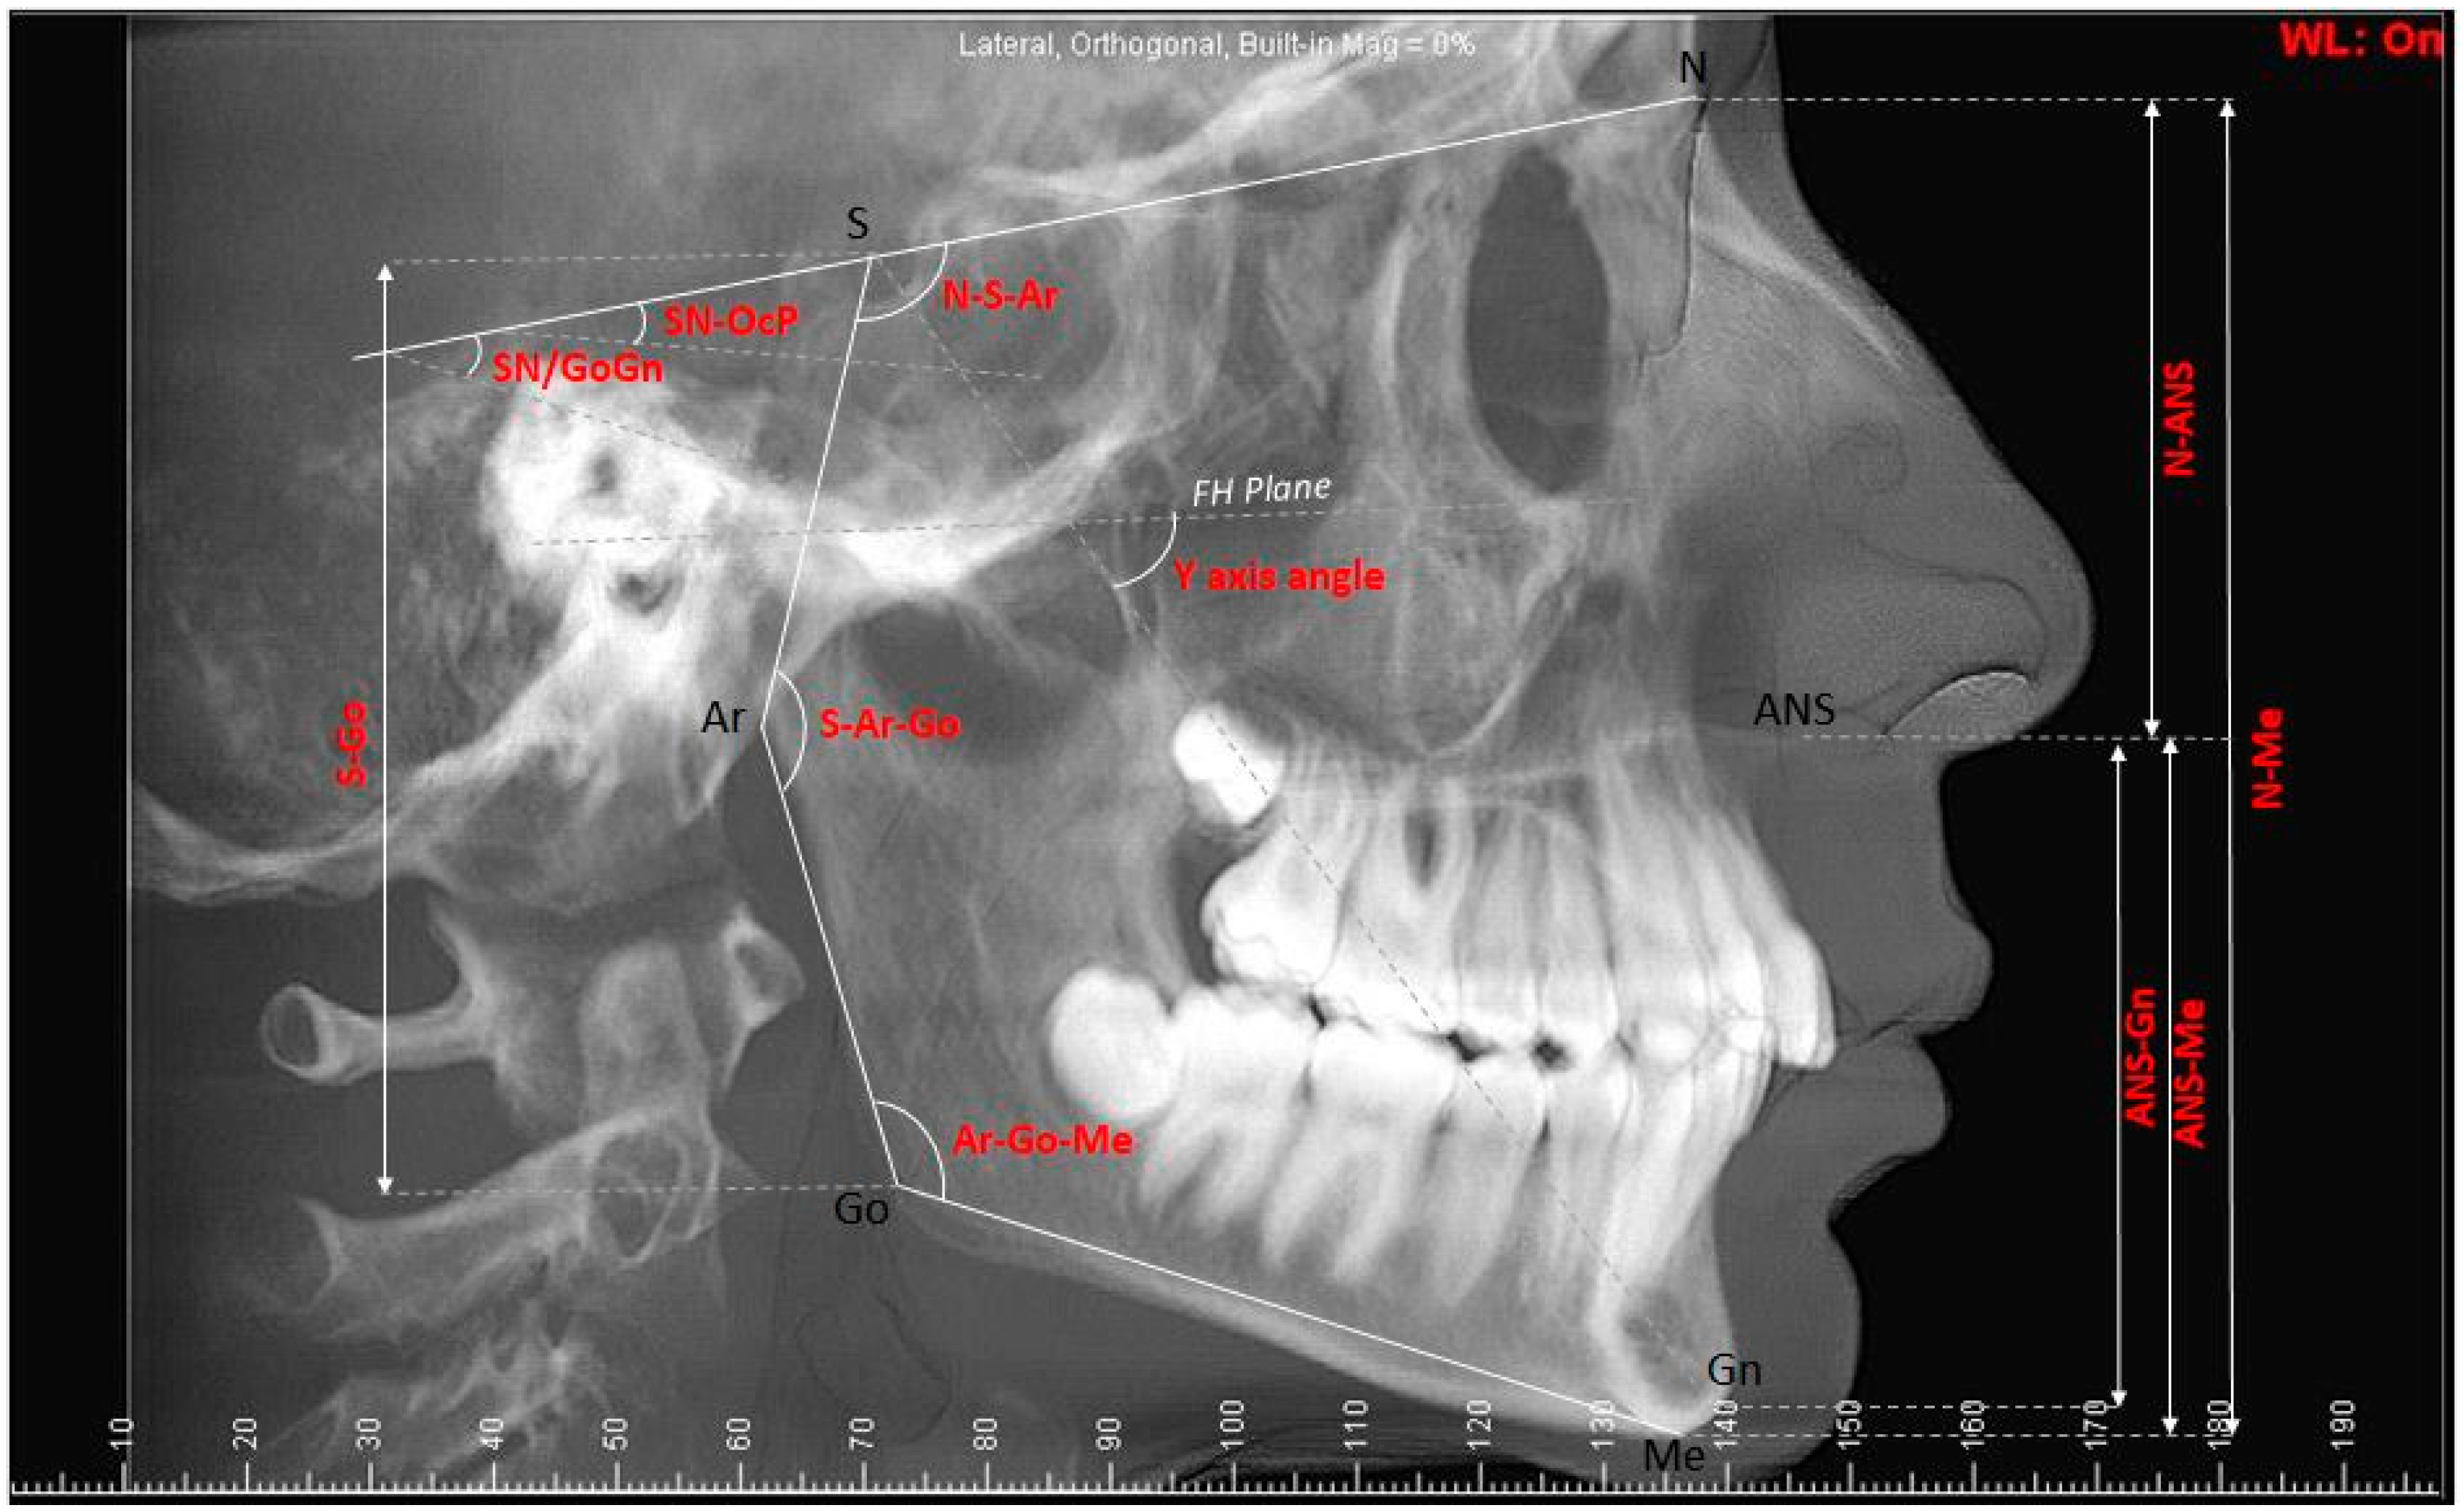

2.1. Cephalometric Measurements